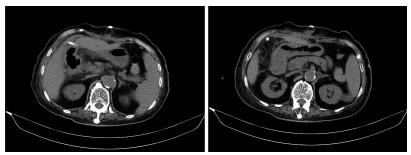

Comorbidity of hepatic cystic echinococcosis with HBV/HCV infection, liver cirrhosis, and hepatocellular carcinoma

Yang MAN, Zhiyi LIN, Zhang MIAO, Lerong YAN, Xiao CHENG, Renyi JING, Rong BAI, Pingwen HUANG, Hongwei ZHANG, Xinyu PENG

2022, 38(3): 601-605. DOI: 10.3969/j.issn.1001-5256.2022.03.020

Abstract(1231) HTML (314) PDF (2056KB)(63)

Abstract:

Objective  To investigate the comorbidity of hepatic cystic echinococcosis with HBV/HCV infection, liver cirrhosis, and hepatocellular carcinoma, and to lay a foundation for further research on the influence of hepatic cystic echinococcosis on HBV/HCV infection, liver cirrhosis, and hepatocellular carcinoma.  Methods  A retrospective analysis was performed for the data of 401 patients with hepatic cystic echinococcosis who were admitted to The First Affiliated Hospital of Shihezi University from 2003 to 2019, and the state of comorbidity of hepatic cystic echinococcosis with HBV/HCV infection, liver cirrhosis, and hepatocellular carcinoma was clarified. The patients with hepatic cystic echinococcosis and chronic HBV/HCV infection were selected as comorbidity group, and the patients with HBV/HCV infection alone were matched as control group. The chi-square test and the Fisher's exact test were used to analyze the state of viral infection and the disease composition of liver cirrhosis and hepatocellular carcinoma.  Results  Of all 401 patients, 38(9.5%) were included in the comorbidity group and 2(0.5%) had liver cirrhosis after HBV/HCV infection, while no patient had hepatocellular carcinoma after HBV/HCV infection. Among the patients with chronic hepatitis B virus infection in the comorbidity group, non-active HBsAg carriers accounted for 81%, HBeAg-positive chronic hepatitis B patients accounted for 9.5%, and HBeAg-negative chronic hepatitis B patients accounted for 9.5%; among the patients with hepatitis B virus infection in the control group, non-active HBsAg carriers accounted for 43%, HBeAg-positive chronic hepatitis B patients accounted for 33%, and HBeAg-negative chronic hepatitis B patients accounted for 19%, with a significant difference between the two groups (P=0.033). There was a significant difference in the HBV RNA clearance rate of the patients with HCV infection between the comorbidity group and the control group (χ2=4.447, P=0.035). In the comorbidity group, the patients with liver cirrhosis accounted for 5.2% and there were no patients with hepatocellular carcinoma, while in the control group, the patients with liver cirrhosis accounted for 18.4% and those with hepatocellular carcinoma accounted for 5.2%; the comorbidity group had significantly lower proportions than the control group (P=0.048).  Conclusion  The proportion of liver cirrhosis patients with hepatic cystic echinococcosis and HBV/HCV infection is lower than that of liver cirrhosis patients with viral hepatitis alone, and there are no cases of hepatocellular carcinoma after HBV/HCV infection. Further multicenter studies are needed to investigate the influence of hepatic cystic echinococcosis on chronic HBV/HCV infection, liver cirrhosis, and hepatocellular carcinoma.